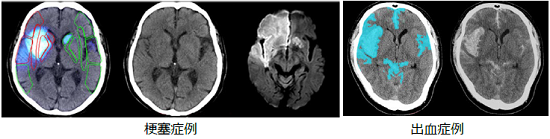

今回、脳卒中の画像診断ワークフローの改善を目的としたアプリケーションから提供を開始する。

ディープラーニング等を用いて設計・開発した技術により、頭部単純CT画像から周囲と比べ低コントラスト及び高輝度の領域を自動で強調表示する。これらは、脳卒中の画像診断において、脳内の出血領域や初期虚血変化等を評価するために用いられる。今後他の疾患へアプリケーションの幅を広げることで、様々な診断支援に活用できる。また、キヤノンメディカルシステムズ(株)PACSと組み合わせることで、医師がワークリスト上で処理状況を確認できる機能や、処理結果をインタラクティブに操作できる機能といった一貫した操作性により、画像診断ワークフローの改善に貢献する。